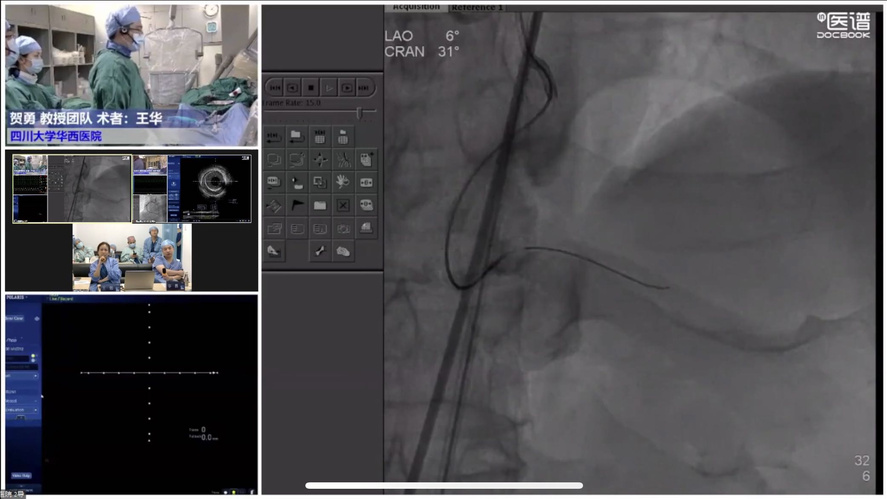

大咖云集的学术会议上,自然不会少了干货满满的学术讲座。四川大学华西医院贺勇教授分享IVUS当前的最新研究进展,同时畅聊标准培训中心的未来发展。南方医科大学南方医院修建成教授分享IVUS在钙化病变中的应用时指出,IVUS辅助可更好的分辨钙化的分布、范围以及严重成都,并在术前、术中、术后等PCI手术的全过程中,帮助选择更好的病变预处理方法以及充分的术后评估,为患者带来更好的预后。复旦大学附属中山医院李晨光教授在FFR指导PCI精准治疗新时代中谈到:无论FFR还是IVUS,都应该让临床医师认识到如何结合不同的影像学与功能学工具,进行多模态的评估患者情况,从而指导PCI精准治疗。吉林大学中日联谊医院童亚良教授分享IVUS的成长秘籍谈到:自己经历定性识图,定量分析、定位匹配,实战应用等环节的学习历练,并且整个团队需要达成共识,强化IVUS”刚需”理念,在分叉、弥漫、无残端CTO等场景大量使用。同济大学附属同济医院刘学波教授在讲座中指出,用好腔内影像学工具,时机十分重要,并在腔内影像学与临床决策中谈到,在冠脉粥样硬化斑块和ACS机制的研究、PCI策略技术优化、术后治疗、新技术应用方面具有指导价值与重大贡献。四川大学华西医院王华教授分享IVUS与FFR联合应用场景时提到当下IVUS与FFR独立使用占用更多手术时间,波士顿科学IVUS+FFR一站式整合应用在制定策略、指导治疗上提供更优选择。此外,四川省科学城医院王栏霖教授、四川大学华西医院黄宝涛教授、宁夏医科大学总医院心脑血管病医院胡光欣教授以病例解读的形式,复盘印象深刻的复杂PCI病例,与线上专家们共同交流探讨,碰撞观点。